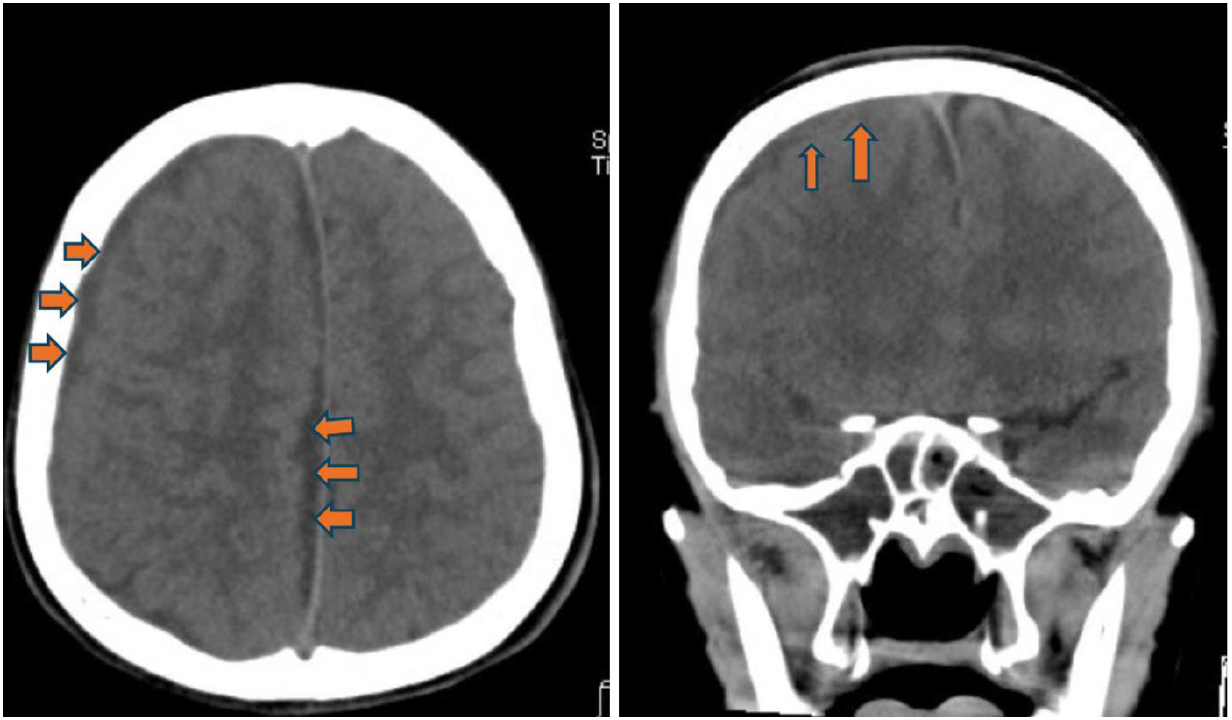

此病童的電腦影像,電腦斷層影像(非注射對比顯影劑),在冠狀切面(圖一)清楚呈現顏面部上頜竇(maxillary sinus)、鼻腔、篩竇(ethmoid sinus)、蝶竇(sphenoid sinus)等腫脹與不均值等病灶,且與健側對照,佐以軸狀切面影像,額竇(frontal sinus)的腫脹與不均值密度病灶(圖二)能較清楚呈現。進一步思考,病童呈現“雙眼球無法往左側移動”“頭痛且意識狀況異常”等,循著解剖器官組織的概念,審視眼部的影像,右眼框骨頭附近篩竇組織腫脹(圖一),審視腦部的影像,不管是軸狀面或是冠狀面影像(圖三),腦部組織腫脹且“推擠”至左側腦部呈現中線偏移。在部分腦部頂葉(parietal lobe)的影像(圖四),呈現相較低密度的“液體”狀成像,結合病童病史和抽血報告,積液部分疑似蓄膿,鑑別診斷可與慢性出血的稍高或等值密度做解析。另外,亦可藉由電腦軟體上可顯示的”Hounsfield unit, HU” 進行分析解讀。

圖三(之1)、頭部電腦斷層軸狀切面(axial view)(左圖)和冠狀切面(coronal view)(右圖):右側腦部呈現明顯腫脹,中線往左側偏移(橘紅色箭頭),右側側腦室(藍色星星)被擠壓,側角結構都已不見。

圖三(之2)軸狀切面(axial view):對比左側腦實質,右側腦實質和腦迴明顯腫脹,白質和灰質之間界限模糊。